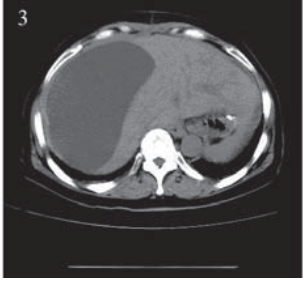

患者,女,66岁。2011年12月因“进食哽噎3 月余”就诊,查胃镜:贲门大弯后壁可见一大小约 3.5 cm×3.9 cm的不规则溃疡,周边堤样隆起。全 身CT等检查提示无其他部位转移,遂于2011年12 月22日在上海中山医院行贲门癌根治术,术中探 查见贲门部病灶,约3 cm×4 cm,质地中等,周围 脏器未见异常,遂行贲门癌根治术,食管胃机械 吻合。术后病理:“贲门”溃疡型腺癌,Ⅱ~Ⅲ级, 侵及胃壁全层及周围脂肪组织,淋巴结(3/20) 见癌转移。TNM分期为:ⅢB期(T4aN2M0), 术后复查CT:两肺少许间质性改变,后腹膜淋巴 结稍大,右肾上极局部形态异常,伴右肾囊肿。 2012年1月27日起予“奥沙利铂+替吉奥”化疗六周 期,期间复查CT无转移依据。2012年8月再次复 查CT:左肺叶间胸膜增厚,右肺上叶可疑小结 节,胃癌术后改变,肝脏小囊肿可能,肝右叶包 膜下包裹性积液,右肾上极梗死后遗改变可能, 右肾小囊肿、小结石,腹盆腔积液,见图 1。查 CA199:154.71 IU/ml,CEA:15.65 ng/ml,肿瘤 进展,遂予“紫杉醇+替吉奥”化疗一周期。2012 年11月初患者出现右上腹胀痛,进食后明显,伴 恶心、呕吐,呕吐物为胃内容物。遂入住我科。 入院查体:右上腹可触及包块,有压痛,中上腹 部可见陈旧性手术疤痕,肝区叩痛明显,余未 见异常。血常规、肝肾功能正常。CA199:143.3 IU/ml,CEA:16.56 ng/ml。腹腔B型超声:腹腔 积液,最大前后径约26 mm;肝包膜下巨大囊性 占位,大小约16.3 cm×9.5 cm,见图 2 。胸部CT未 见异常。腹盆部CT:胃癌术后改变,肝脏小囊肿 可能,肝右叶包膜下包裹性积液较前明显增加, 右肾上极梗死后遗改变可能,右肾小囊肿、小结 石,右肾轻度积水,腹盆腔积液,见图 3。

图 3 肝包膜下巨大囊性转移瘤患者腹部CT Figure 3 Abdominal CT of huge cystic metastatic tumor of hepatic subcapsular The encapsulated fluid undethe right lobe of the liver capsule was increased significantly |